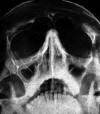

Рис. 167. Рентгенограмма череда в подбородочно-носовой проекции ребенка 9 лет. В

правой верхнечелюстной пазухе нежные пристеночные наслоения (набухание слизистой

оболочки).